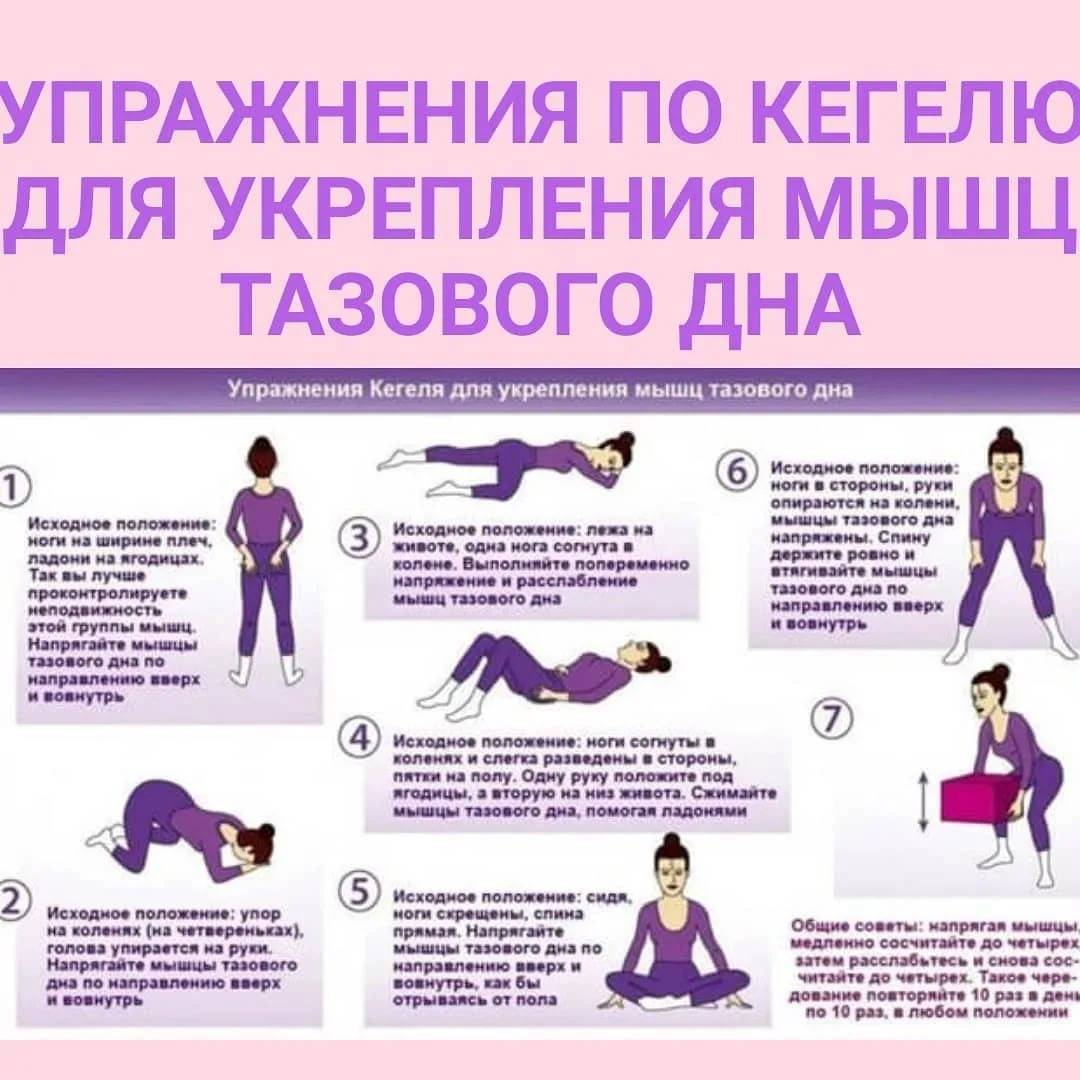

Гимнастика Кегеля для мужчин: упражнения для простаты